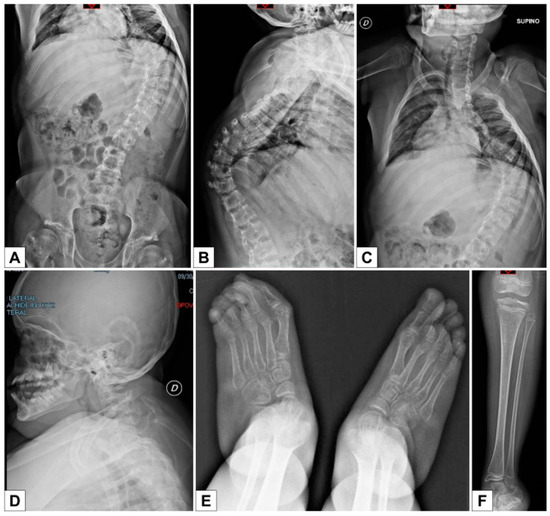

3.3. Third Patient

3.3.1. Clinical Report

- the radiological signs, which are the main indicator for discriminating spEDS-B4GALT7, associated with radioulnar synostosis, and spEDS-B3GALT6, characterized by kyphoscoliosis (congenital or early onset and progressive) and by the skeletal signs of SEMDJL1 (platyspondyly, short iliac bones, elbow dislocation).